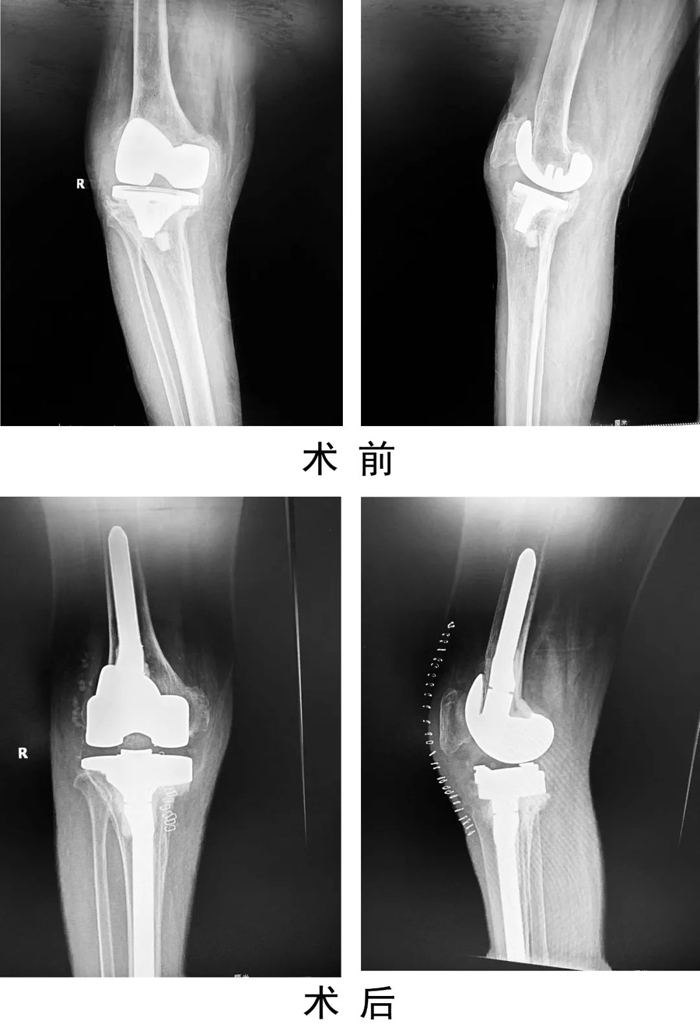

患者,女,69歲,因“右膝人工關(guān)節(jié)置換術(shù)后6年,疼痛伴活動受限1年”入住關(guān)節(jié)運動醫(yī)學二科。術(shù)前X線示右膝人工關(guān)節(jié)假體松動,感染指標檢查:C反應蛋白80mg/L,血沉20mm/h,關(guān)節(jié)穿刺培養(yǎng)提示表皮葡萄球菌感染。查體見有膝部有一長約15cm手術(shù)疤痕,皮溫高,關(guān)節(jié)腫脹,右膝關(guān)節(jié)活動受限。入院診斷為:右膝關(guān)節(jié)假體周圍感染,人工假體松動,右脛骨平臺骨缺損。

患者入院后,關(guān)節(jié)運動醫(yī)學二科手術(shù)團隊制定嚴密的手術(shù)計劃,為患者實施了一期右膝人工關(guān)節(jié)翻修術(shù),一次手術(shù)清除原假體,徹底清創(chuàng)后,重新植入翻修假體。手術(shù)后患者右膝刀口一期愈合出院,患膝功能良好,疼痛緩解。復查感染指標C反應蛋白4.45mg/L。